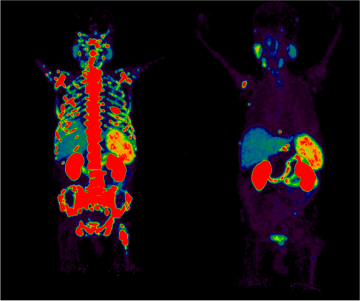

Dual thermal imaging of a human body, highlighting skeletal and organ structures.

Our specialists can treat certain cancers and benign diseases by administering small amounts of radioactive drugs. Some of these treatments use theranostics – a type of precision medicine which specifically targets diseased cells and organs. Nuclear medicine therapeutics and theranostics are safe and often have fewer side effects than conventional treatments.